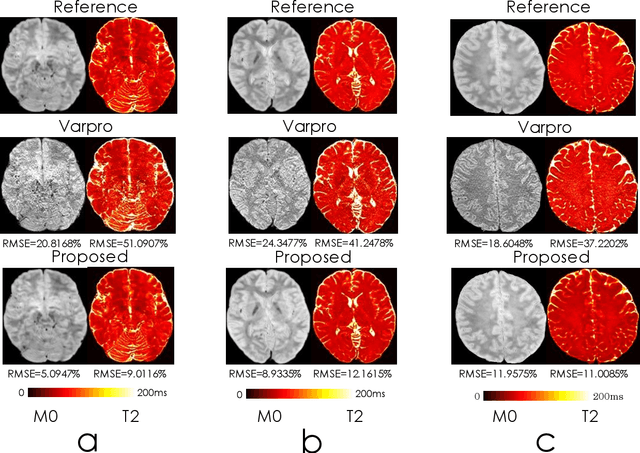

Abstract:We propose an unsupervised convolutional neural network (CNN) for relaxation parameter estimation. This network incorporates signal relaxation and Bloch simulations while taking advantage of residual learning and spatial relations across neighboring voxels. Quantification accuracy and robustness to noise is shown to be significantly improved compared to standard parameter estimation methods in numerical simulations and in vivo data for multi-echo T2 and T2* mapping. The combination of the proposed network with subspace modeling and MR fingerprinting (MRF) from highly undersampled data permits high quality T1 and T2 mapping.